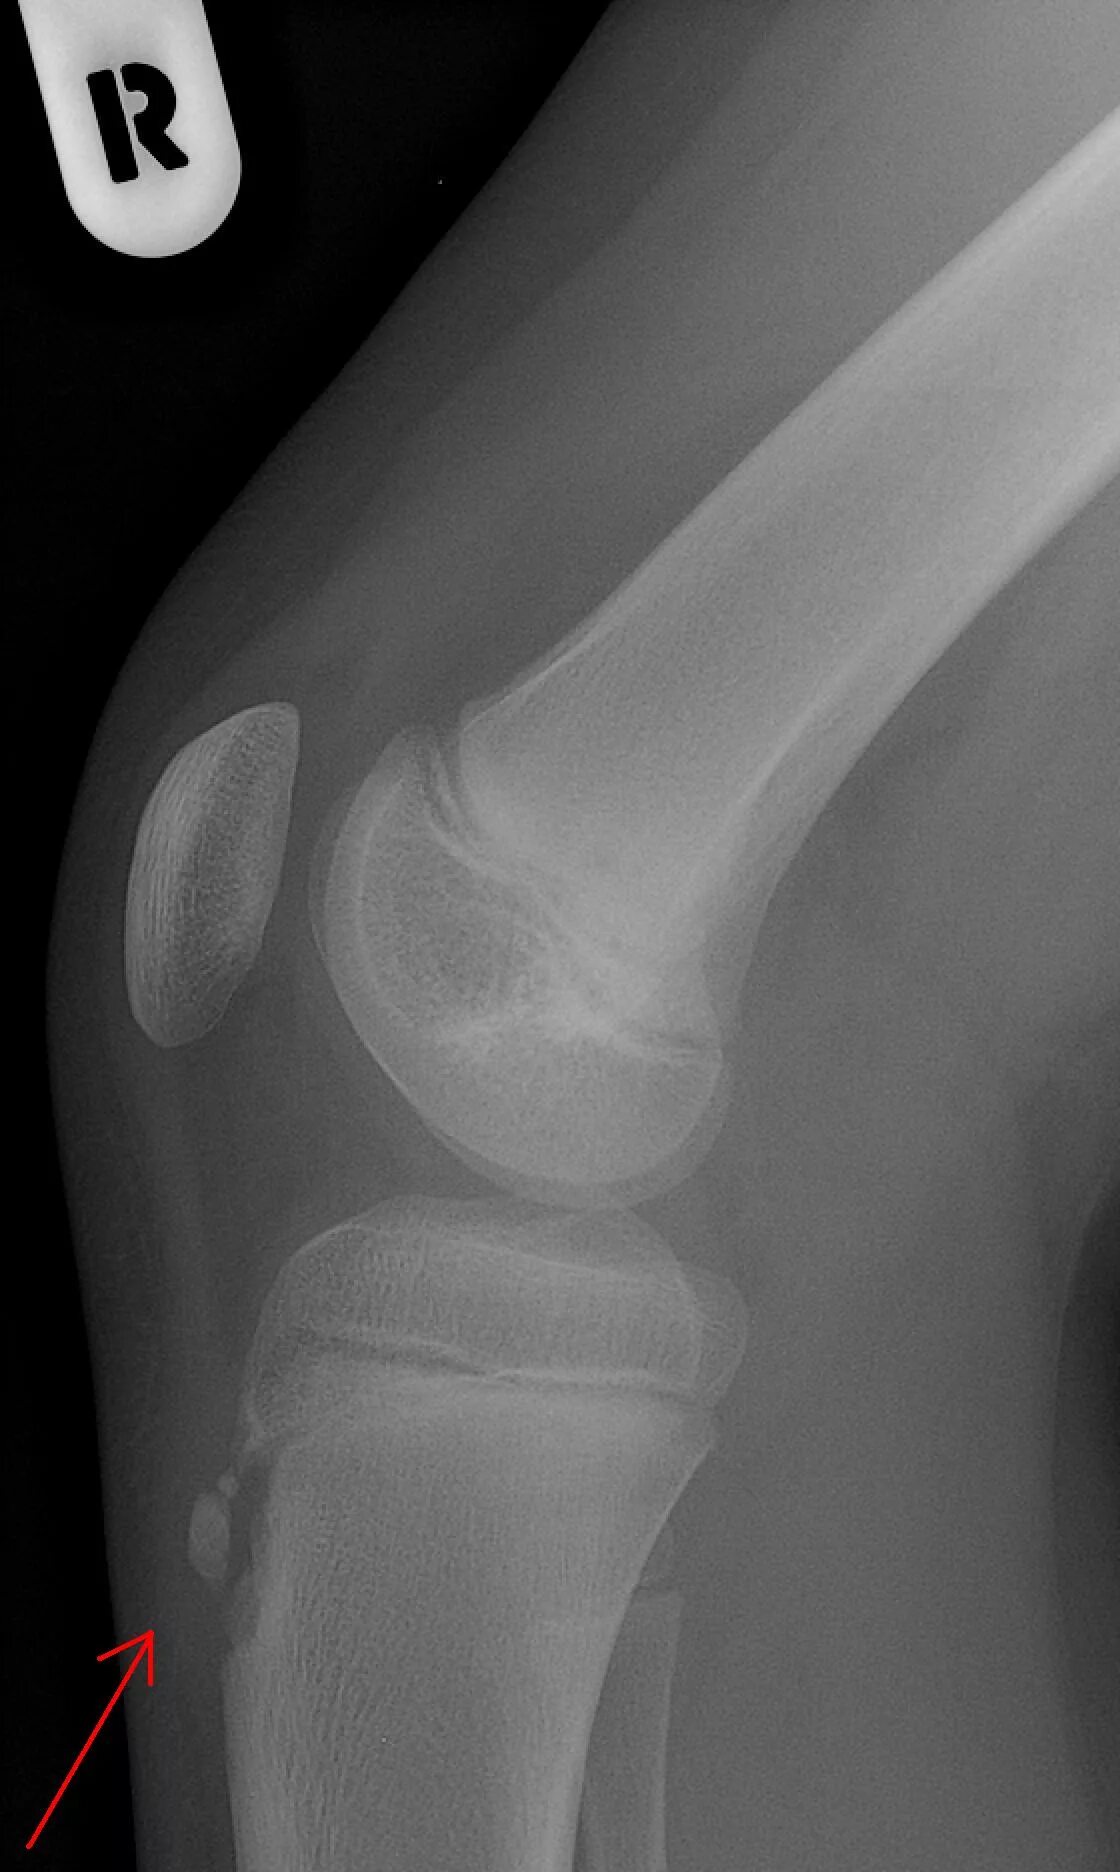

Код мкб шляттера